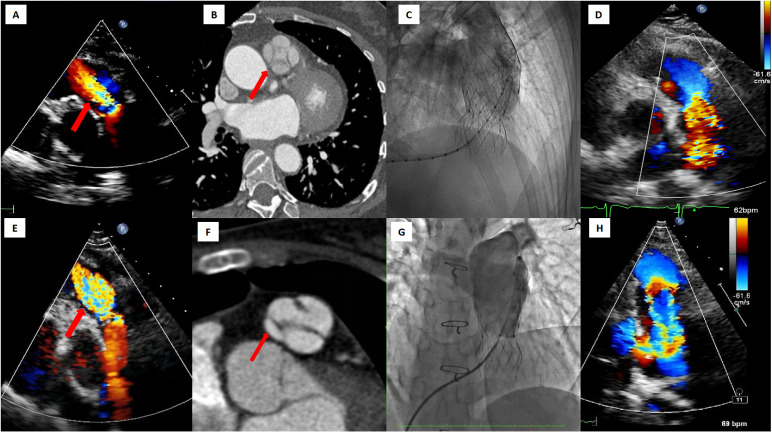

Transcatheter Pulmonary Valve Implantation in Patients with Quadricuspid Pulmonary Valve Regurgitation.

Abstract Image